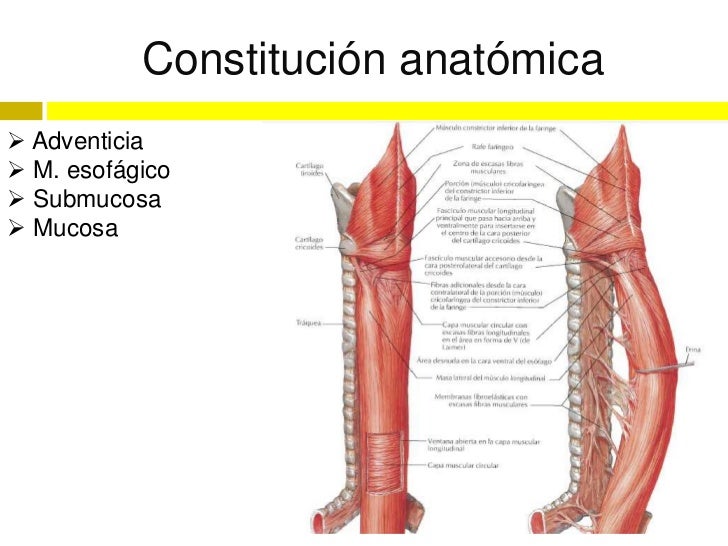

Por su cara posterior se relaciona con la porción cervical del esófago.